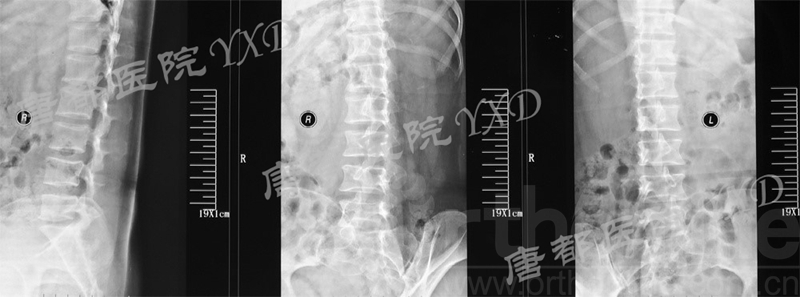

影像学检查:

诊断:腰椎间盘突出症术后复发

手术方案:显微镜辅助MI-TLIF腰椎翻修术

术中视频:http://api.orthonline.com.cn/attach/Case2.mp4(术中发现因前三次侧路及后路内镜手术的操作,术区大量瘢痕组织增生、与神经粘连严重;此外,摘除头侧游离髓核时连接有软骨终板脱落;在显微镜操作下,安全地将神经进行充分松解,压迫神经的游离髓核及软骨终板彻底清除。无手术并发症)